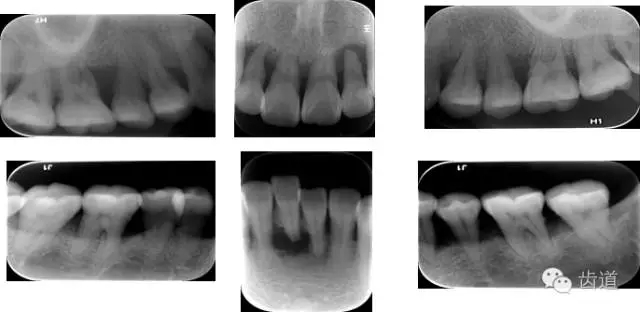

6、輔助檢查

X線:根尖片、曲面斷層片(牙槽嵴頂,水平垂直吸收,程度)

21.webp.jpg

22.webp.jpg

23.webp.jpg

大表